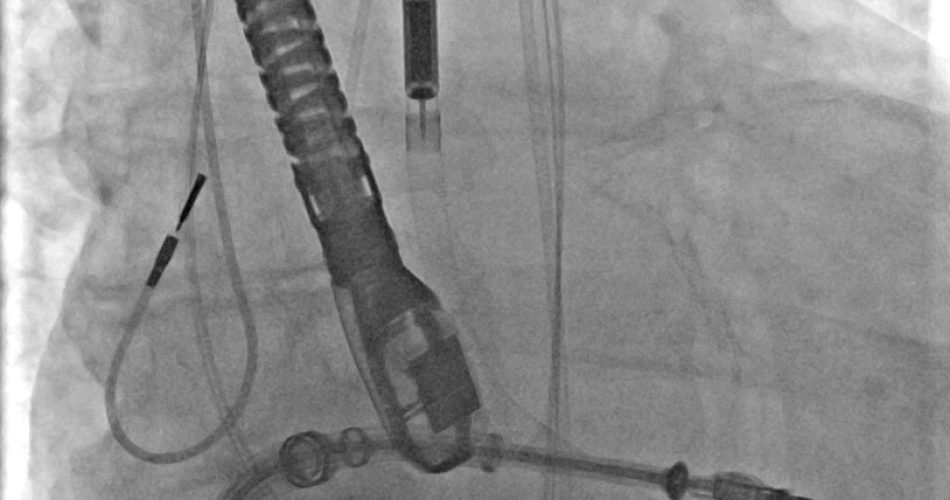

Procedura impella

Nei giorni scorsi, presso il Bonomo di Andria, per la prima volta in Puglia, è stato eseguito su un paziente 62enne un complesso intervento combinato di riparazione trans catetere di mitrale con il supporto del sistema di assistenza ventricolare Impella, che funge da pompa microassiale intravascolare per supportare temporaneamente la funzione cardiaca, del ventricolo sinistro, in caso di grave sofferenza o shock cardiogeno.

“A causa della severa disfunzione della contrattilità cardiaca – spiega il dott. Claudio Larosa, cardiologo emodinamista che ha eseguito l’intervento – anche l’intervento trans catetere avrebbe comportato notevoli rischi procedurali. Si è, pertanto, pianificata la riparazione della valvola mitralica trans catetere con utilizzo contemporaneo di un sistema di assistenza ventricolare sinistra. Tale dispositivo, chiamato Impella, è stato posizionato all’interno del cuore attraverso un accesso arterioso di grosso calibro ad ha avuto l’obiettivo di supportare la funzione del cuore, severamente compromesso durante l’intera durata della procedura interventistica, evitando che il paziente potesse scompensarsi. L’intervento è stato portato a termine con successo ed il paziente è stato estubato e risvegliato già a fine procedura ed è stato trasferito, in buone condizioni, in terapia intensiva cardiologica dove è stato prontamente assistito dal personale di reparto”.